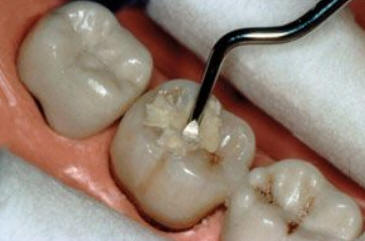

Imagen digital que representa la microfiltración y penetración del sellante realizado.

Microfotografía: Muestra como el sellador obtura la caries subyascente, evitando su avance.

Código 3 (Caries moderada) in vitro. Los códigos 3 in vivo debe ser sellado para evitar el avance del proceso carioso. (MNO)

Código 4 (Caries moderada) in vitro. Los códigos 4 in vivo deben ser tratados en forma operatoria con preservación dental (MOPD), porque presentan dentina infectada.